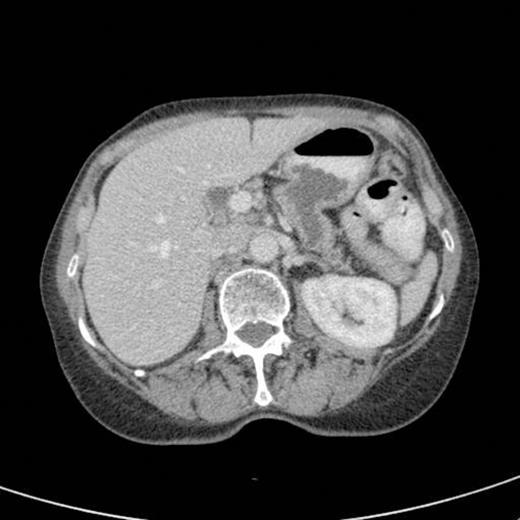

A subsequent CT scan done a year later confirmed the persistence of the gastro pancreatic fistula with polypoid herniation into the stomach and this was thought to represent main duct IPMN with mucinous tumour herniation into stomach (Fig 4). An upper GI endoscopy confirmed the gastric opening of the fistula at 50 cm on the lesser curve with a mucus plug sealing the opening (Fig 5). Biopsies were taken from around the fistulous opening and this was reported as non-specific inflammation. Again, a surgical option was offered that was declined by the patient and hence it was decided to continue with regular follow up and conservative management.